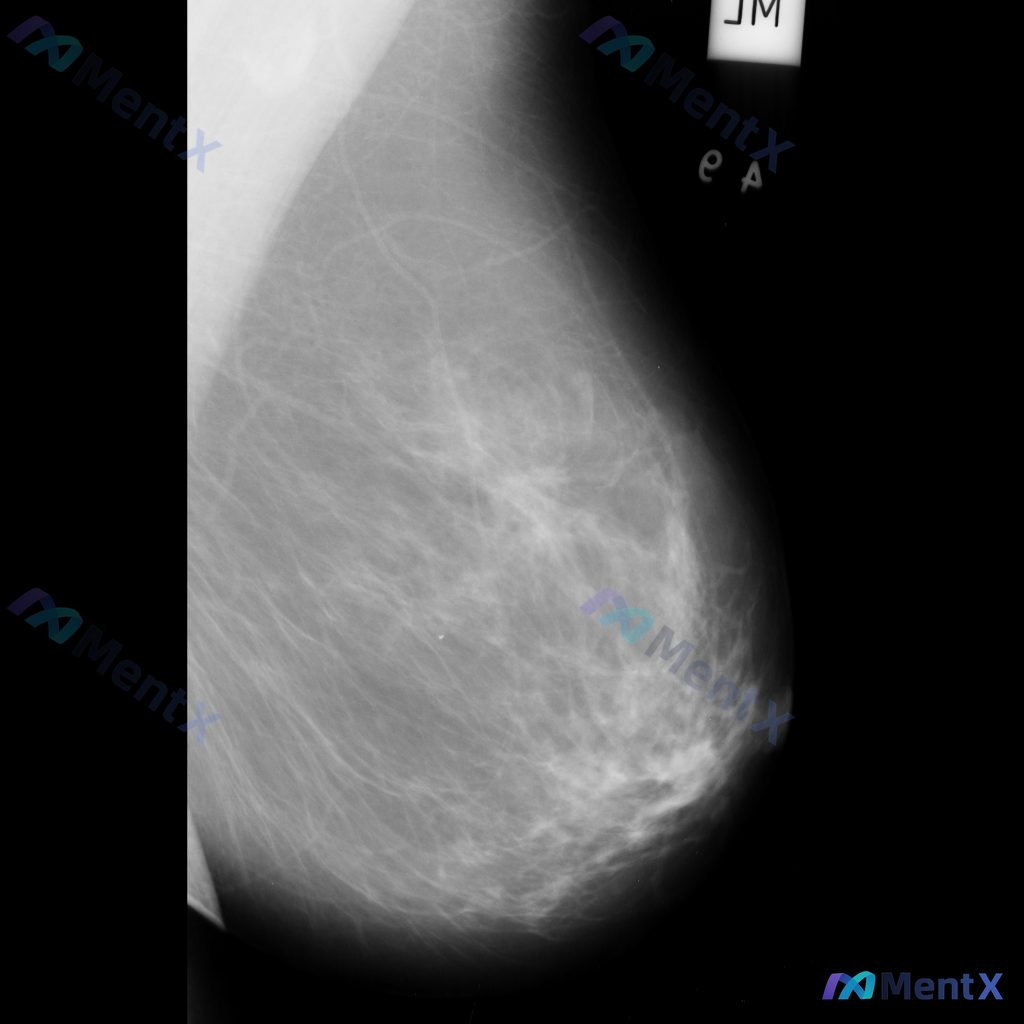

整理到一张乳腺钼靶影像资料,大家一起讨论下。 影像表现大概是这样: - 异常区域位于乳腺下象限偏外侧 - 可见一局限性致密影,形态大致呈卵圆形或不规则形 - 边缘部分清晰,局部可能模糊或有细微毛刺样改变 - 致密影密度高于周围脂肪组织,与纤维腺体组织密度相似或略高 - 周围乳腺小梁结构似有轻微的牵拉...